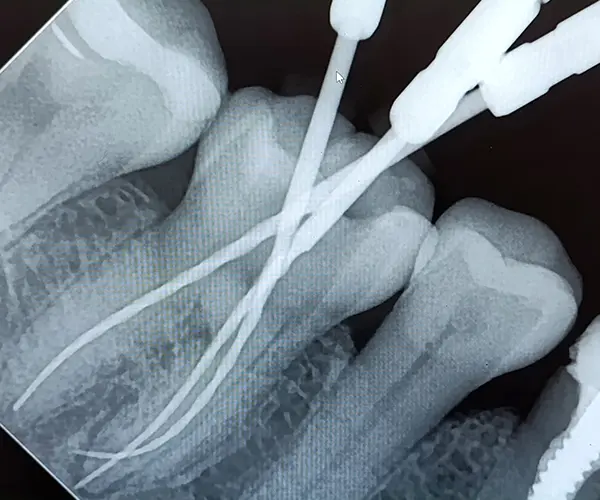

Контроль: рентгеновские снимки